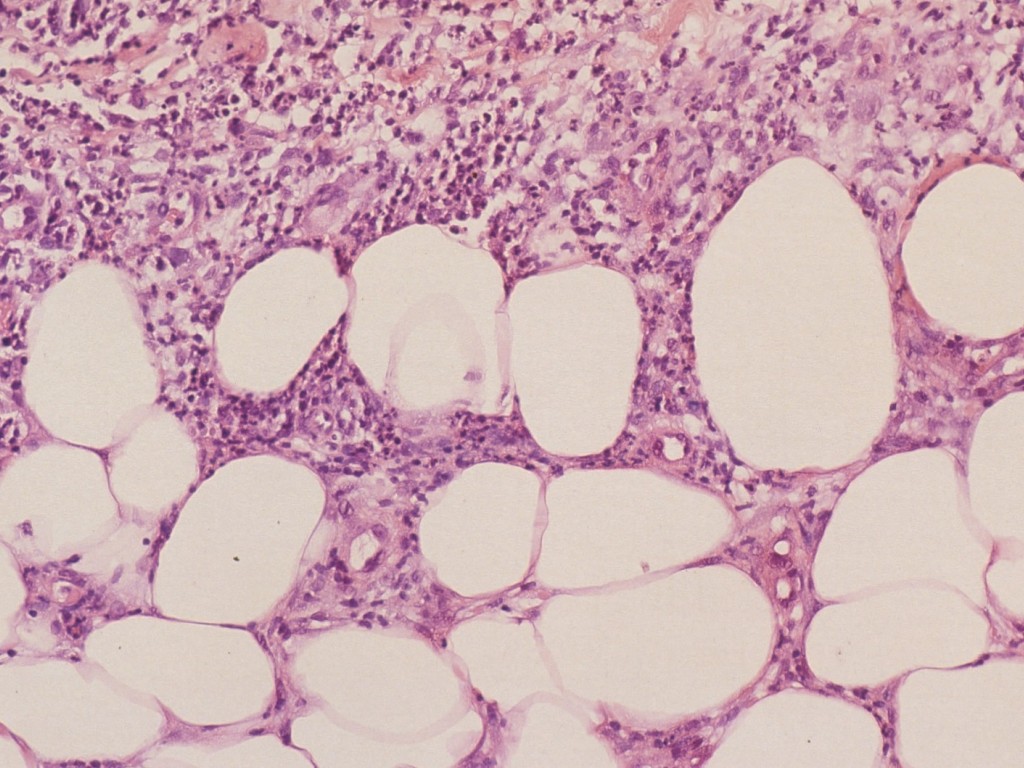

In de epidermis geen bijzonderheden. In de dermis is enig perivasculair lymfocytair infiltraat aanwezig. Typisch in vroege laesies is een ontsteking in de septa (tussen lobuli in) en rond de septale bloedvaatjes. Vanuit de bindweefselsepta breidt het infiltraat zich ook uit tussen de vetcellen van de subcutis, dus lobulair, waardoor het geheel aan kant doet denken (lacelike fashion). Het infiltraat bestaat uit lymfocyten / histiocyten en enkele polynucleaire granulocyten, soms enkele eosinofiele granulocyten. Het septale collageen toont oedeem en fibrinoïde degeneratie. Er is geen vetnecrose of abcesvorming. Het betreft primair een vasculitis van kleine en middelgrote venen, gepaard gaande met endotheel proliferatie, verdikking van de intima en ontsteking van de vaatwand. Occlusie (tromboflebitis, hemorrhagieën) komt zelden voor. Vaak ziet men erytrocyten extravasculair. Bij oude laesies zijn de polynucleairen verdwenen; er zijn infiltraatnoduli, samengesteld uit radiaal gegroepeerde histiocyten vaak met vreemd-lichaam reuscellen, soms tuberculoïde structuren (epitheloïde cellen, granulomen).

Erythema nodosum histologie Erythema nodosum histologie

erythema nodosum erythema nodosum

Erythema nodosum histologie Histologie erythema nodosum

erythema nodosum ingescande coupe (zoom)

Bron hoge resolutie PA-foto's: Kevin Kwee en Afdeling Pathologie MUMC. Klik op de afbeelding om in te zoomen.